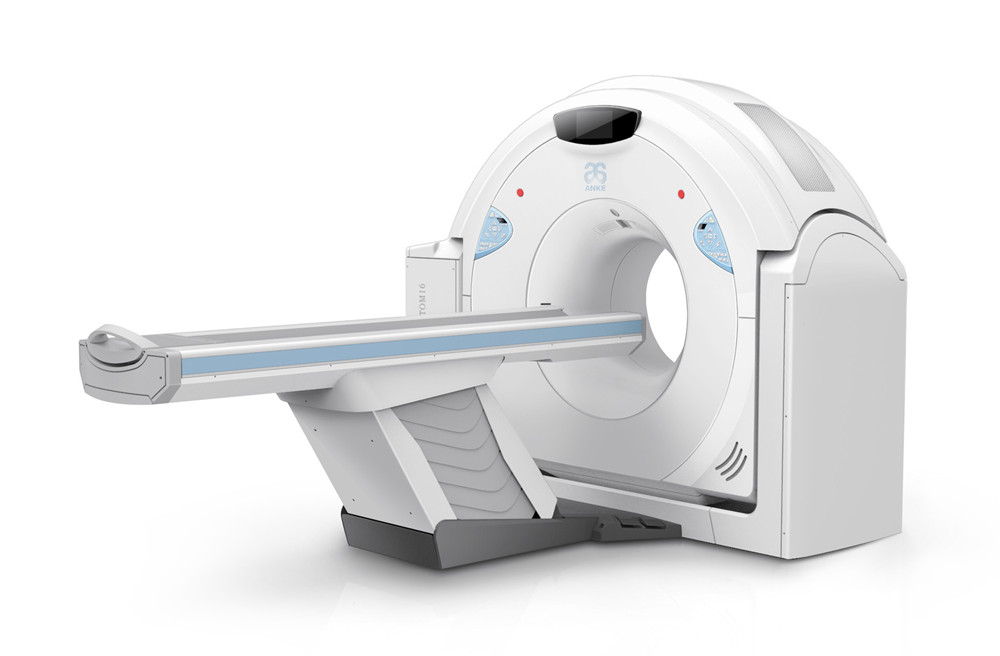

案例展示 ∥ 影像类设备 ∥ ANATOM 16层螺旋CT

作为国内资深的CT生产厂家,该机型具备了与国际主流产品相同的技术能力,为此需要开发全新的产品外观及结构,以适应新的产品形象。大型医疗器械涉及到材料,力学,工艺,运动机构,人机功效等不同的各种学科知识,无限空间设计团队为了整合不同学科要求而做出平衡性设计,同时突出设计亮点,为产品赋予自身特有的产品形象。

ANATOM 16层螺旋CT是针对国内基层医疗机构对高端CT的需求而推出一款划时代产品,采用了十多项创新性技术,它对于我们国内广大县乡日益增加的肿瘤、心脑血管疾病等诊断有着重要意义,凭借卓越的影像质量,ANATOM 16可以帮助医生进行早期、微小病变以及心脑血管疾病等全身各个系统的诊断及筛查,进而给患者及时恰当的治疗,为患者的早期治疗赢得时机。

客户 | 安科医疗

项目 | ANATOM 16层螺旋CT

年份 | 2013

client | ANKE Tech

year | 2013